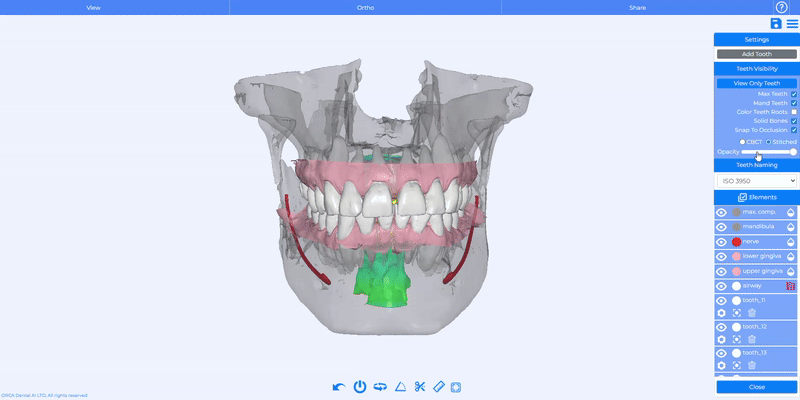

Multi-Tooth Selection & Movement in the Planned Stage

We’ve just made orthodontic planning faster and easier than ever: you can now select and move multiple teeth at once in the Planned Stage.

How Does It Work?

Hold down CTRL while clicking to select several teeth, and use the standard movement tools to move them simultaneously.

Enhanced Visibility Controls

You now have full control over visibility in the Tooth Panel: adjust the opacity of gingiva, bone, airway, and nerve with dedicated sliders.

Simply click the Drop icon to reveal per-element opacity controls and refine your view for more accurate treatment planning.

Solid Bones Toggle

We added a new Solid Bones checkbox to the Tooth Panel. It’s enabled by default and immediately switches bones to a solid rendering, making it easier to review anatomical structures and plan interventions.

You can easily activate or disable the “Solid bones” feature anytime with a quick toggle in the drop-down menu.

Snap to Occlusion

A new Snap to Occlusion feature is now available for stitched cases. When activated, it automatically aligns the models so the upper and lower teeth fit together correctly, making it easier for clinicians to assess bite relationships with greater accuracy.

You can easily activate or disable Snap to Occlusion anytime with a quick toggle in the drop-down menu.